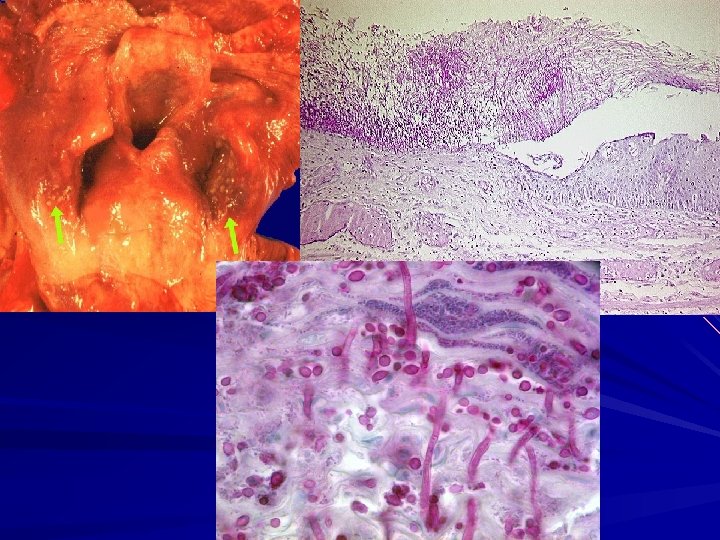

The final common pathway for all is – severe acute inflammation, – superficial necrosis (erosion), – ulceration with the formation of granulation tissue, – accumulation of adherent purulent debris, – and eventual fibrosis. In infectious dieseases: – Candidiasis: gray-white pseudomembranes – Herpes and cytomegalovirus: punched-out ulcers, inclusions – Pathogenic bacteria: bacterial invasion with ulcerations.

Candida albicans Superficial, curdy, gray to white inflammatory membrane composed of matted organisms fibrinosuppurative exudate with an underlying erythematous inflammatory base Risk factors: – Diabetes mellitus, – neutropenia, – immunoincompetent, – AIDS, – Xerostomia, antibiotic therapy.